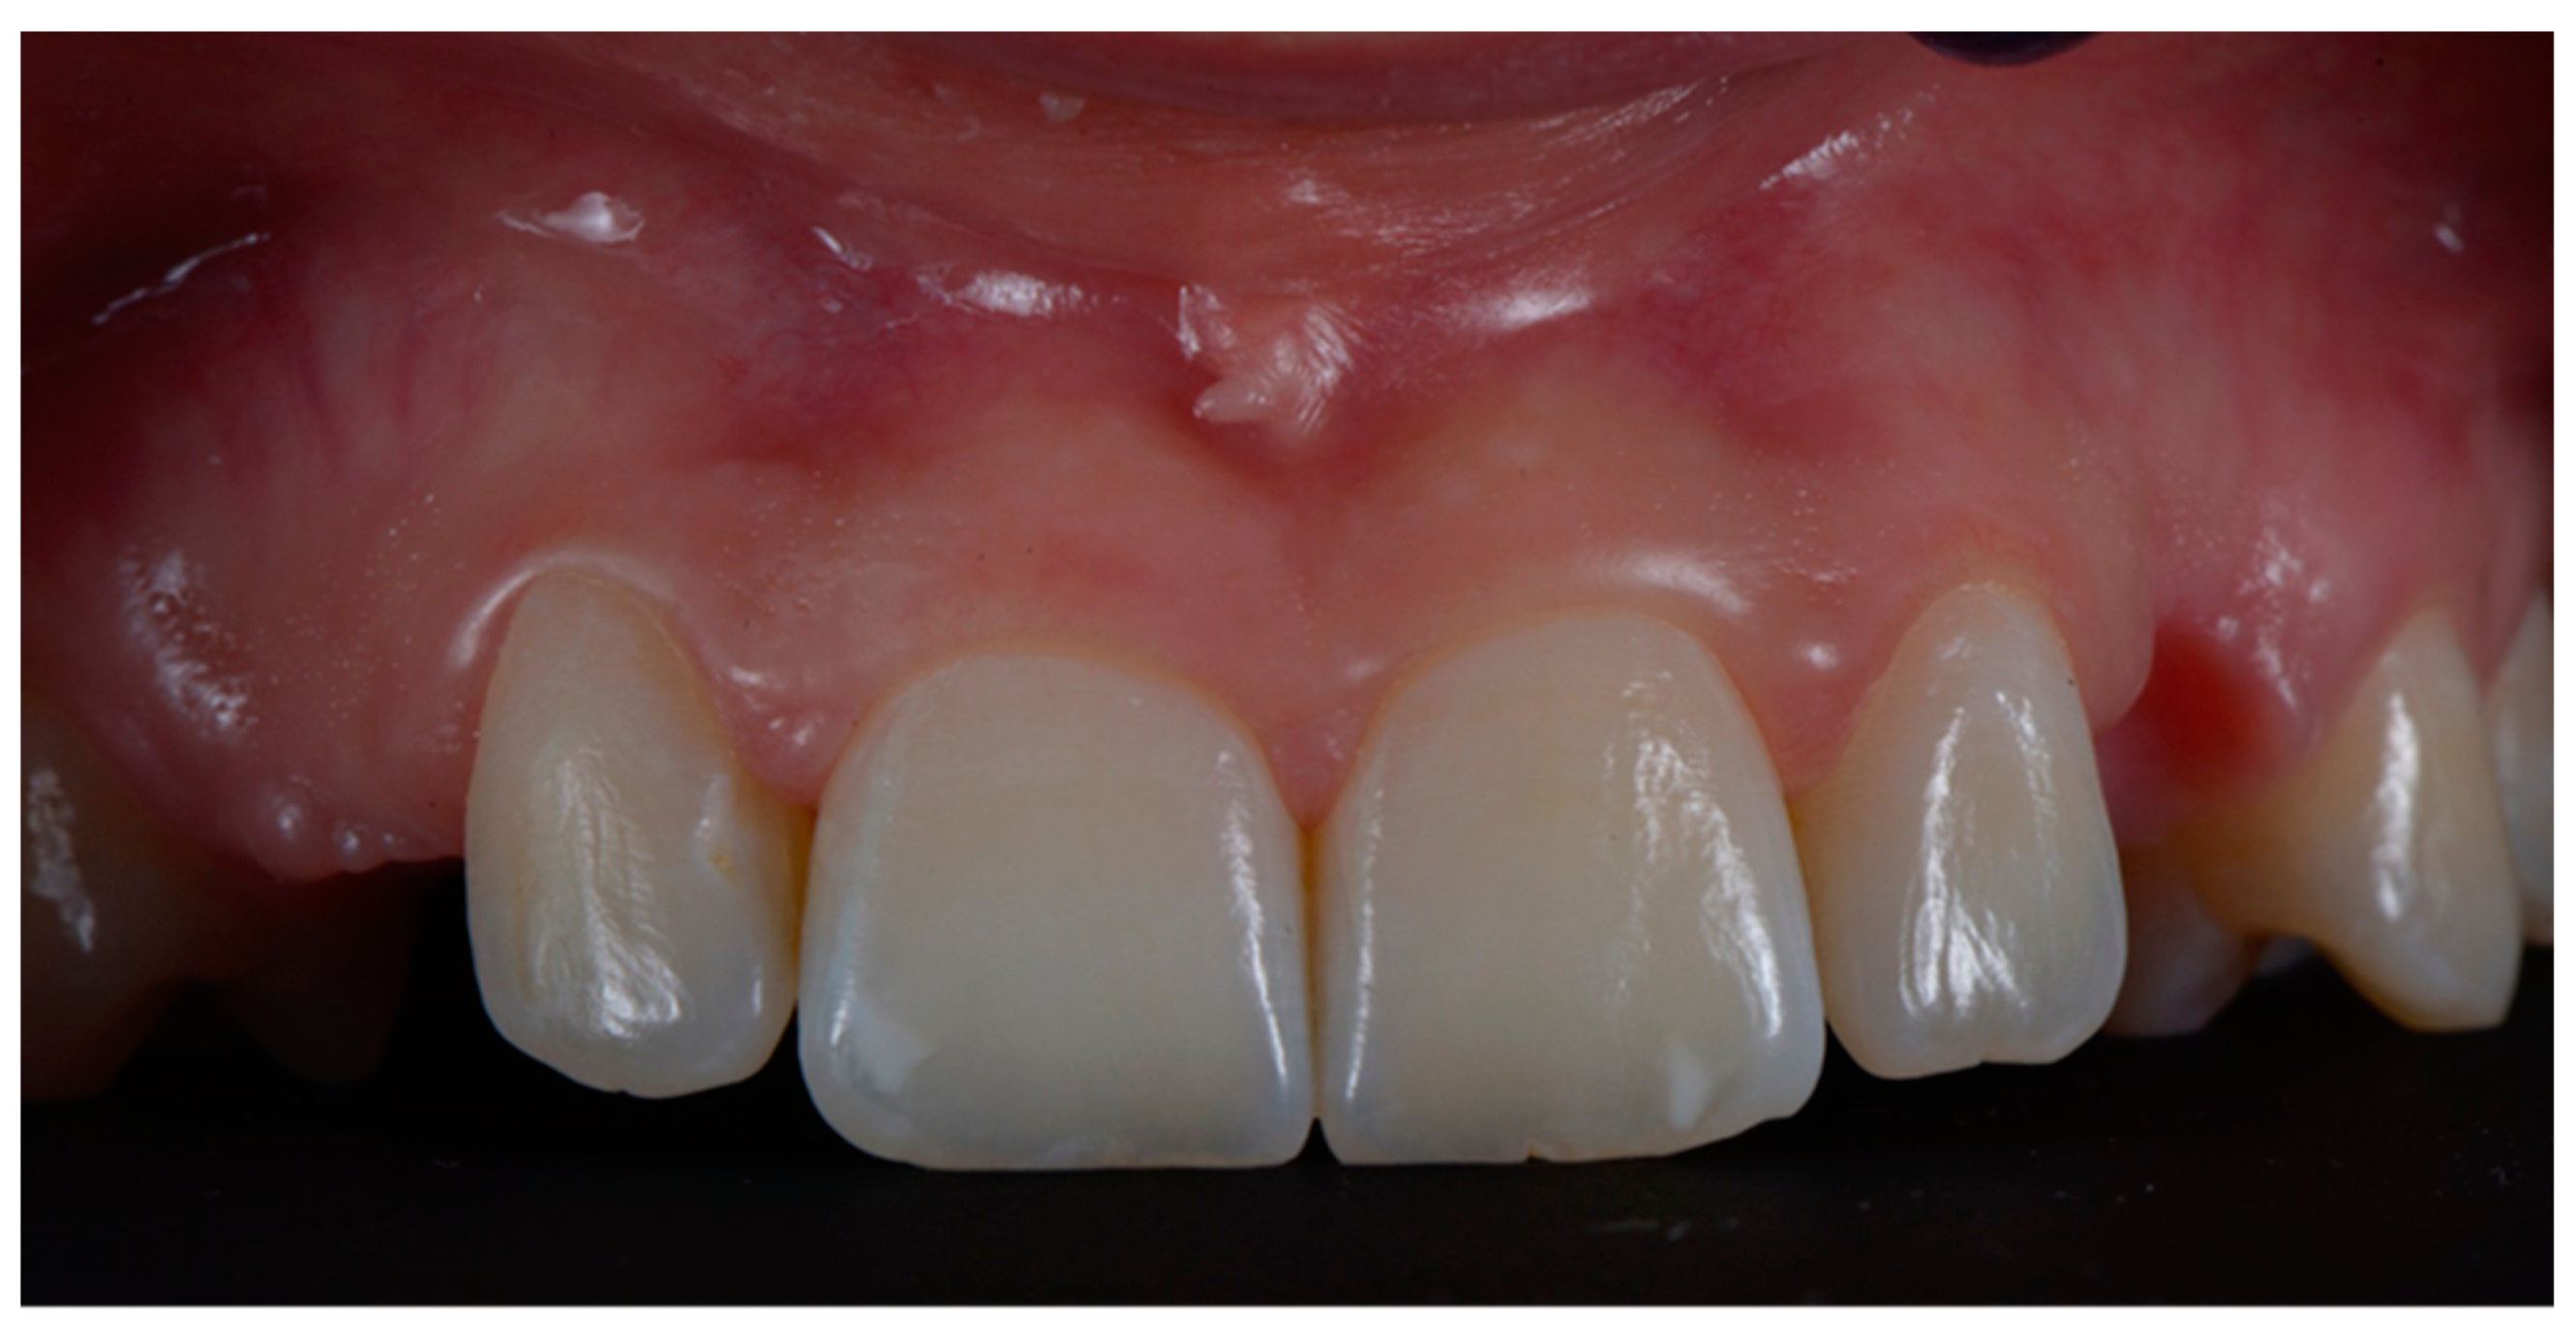

2.3. Surgical and Prosthetic Workflow

2.4. Outcome